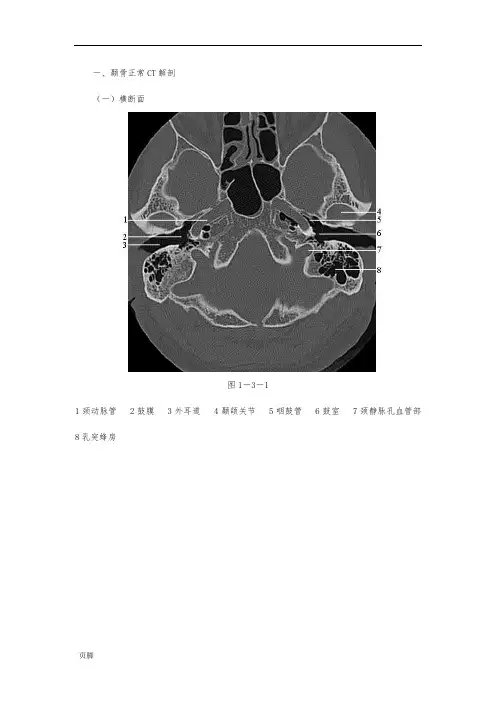

一、颞骨正常CT解剖(一)横断面图1-3-11颈动脉管 2鼓膜 3外耳道 4颞颌关节 5咽鼓管 6鼓室 7颈静脉孔血管部8乳突蜂房图1-3-21耳蜗 2鼓室 3耳蜗水管 4砧骨长脚 5锤骨颈 6外耳道 7蜗窗 8面神经管乳突段9颈静脉窝图1-3-31锤骨颈 2砧镫关节 3面神经管后膝 4鼓室窦 5耳蜗 6匙突 7镫骨 8锥隆起9耳蜗水管图1-3-41耳道 2耳蜗 3面神经管鼓室段 4前庭窗 5锤骨头 6锤砧关节 7砧骨短脚 8前庭 9后半规管图1-3-51面神经管迷路段 2面神经管膝部 3耳道 4前庭导水管 5前庭 6窦入口 7外半规管 8后半规管 9岩鳞隔 10乳突窦图1-3-61上半规管 2后半规管 3上半规管 4总脚 5弓下管(二)冠状面图1-3-7 1耳蜗 2颈动脉管 3岩枕缝 4鼓室图1-3-81Prussak间隙 2耳蜗 3颈动脉管 4岩枕缝 5面神经管膝部 6鼓室盾板 7锤骨图1-3-91耳蜗 2锤骨柄 3鼓膜 4面神经管迷路段 5面神经管鼓室段图1-3-101上半规管 2岩鳞隔 3外半规管 4砧镫关节 5前庭窗 6镰状嵴 7前庭8面神经管鼓室段 9耳蜗图1-3-11 1上半规管 2前庭 3外半规管 4蜗窗龛图1-3-121岩乳管 2上半规管 3外半规管 4锥隆起 5颈静脉窝 6总脚 7面神经管第二膝8鼓室窦图1-3-131枕大孔 2面神经管乳突段 3舌下神经管 4后半规管 5颈静脉结节(三)斜矢状面:图1-3-141前庭水管 2乳突气房 3乙状窦 4耳道 5颈动脉管 6颈静脉窝图1-3-151上半规管 2后半规管 3前庭水管 4乳突气房 5乙状窦 6总脚 7耳蜗 8镰状嵴9颈动脉管 10单孔 11颈静脉窝图1-3-161上半规管 2前庭 3外半规管 4后半规管 5前庭上神经管 6面神经管迷路段 7耳蜗图1-3-171上半规管 2外半规管 3面神经管后膝 4面神经管乳突段 5面神经管前膝 6面神经管鼓室段 7鼓室 8茎乳孔图1-3-181砧骨体 2窦入口 3乳突窦 4砧骨短脚 5鼓后棘 6锤砧关节 7锤骨头 8锤骨柄9岩鼓裂10鼓前棘图1-3-191乳突气房 2外耳道 3颞颌关节。